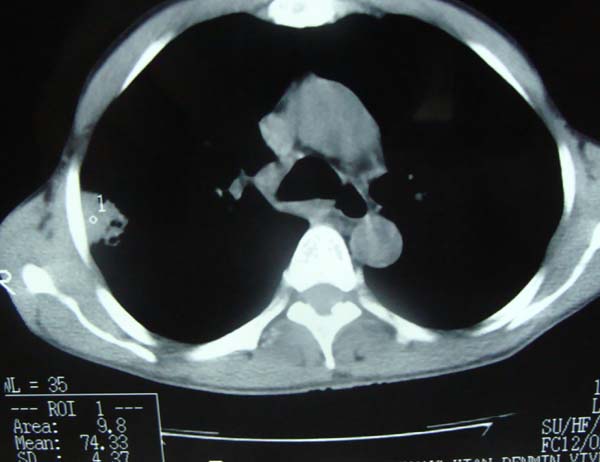

以下是引用pujunzhi在2009-6-21 21:48:00的发言:[br]右肺上叶后段见一空洞性病灶,灶周有渗出即晕征,右肺门肿大---可考虑感染性空洞和癌性空洞,先抗炎抗痨后复查并完善相关检查。有癌性空洞伴肺门淋巴结转移的可能。